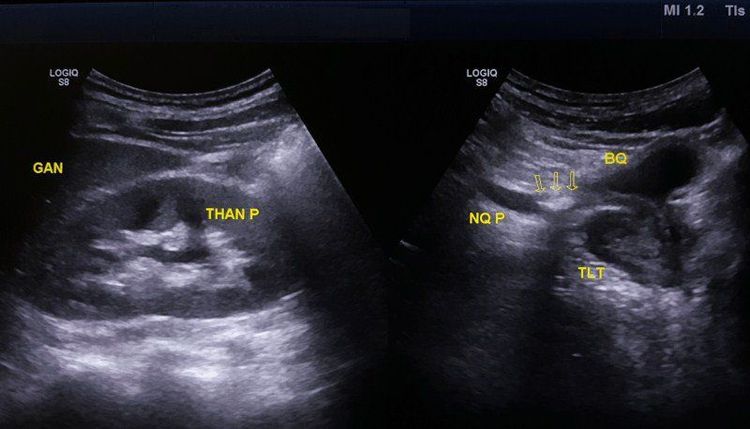

• Siêu âm đánh giá được kích thước và vị trí của sỏi như sỏi thận, sỏi bàng quang, sỏi niệu đạo...

Hình ảnh siêu âm sỏi niệu quản